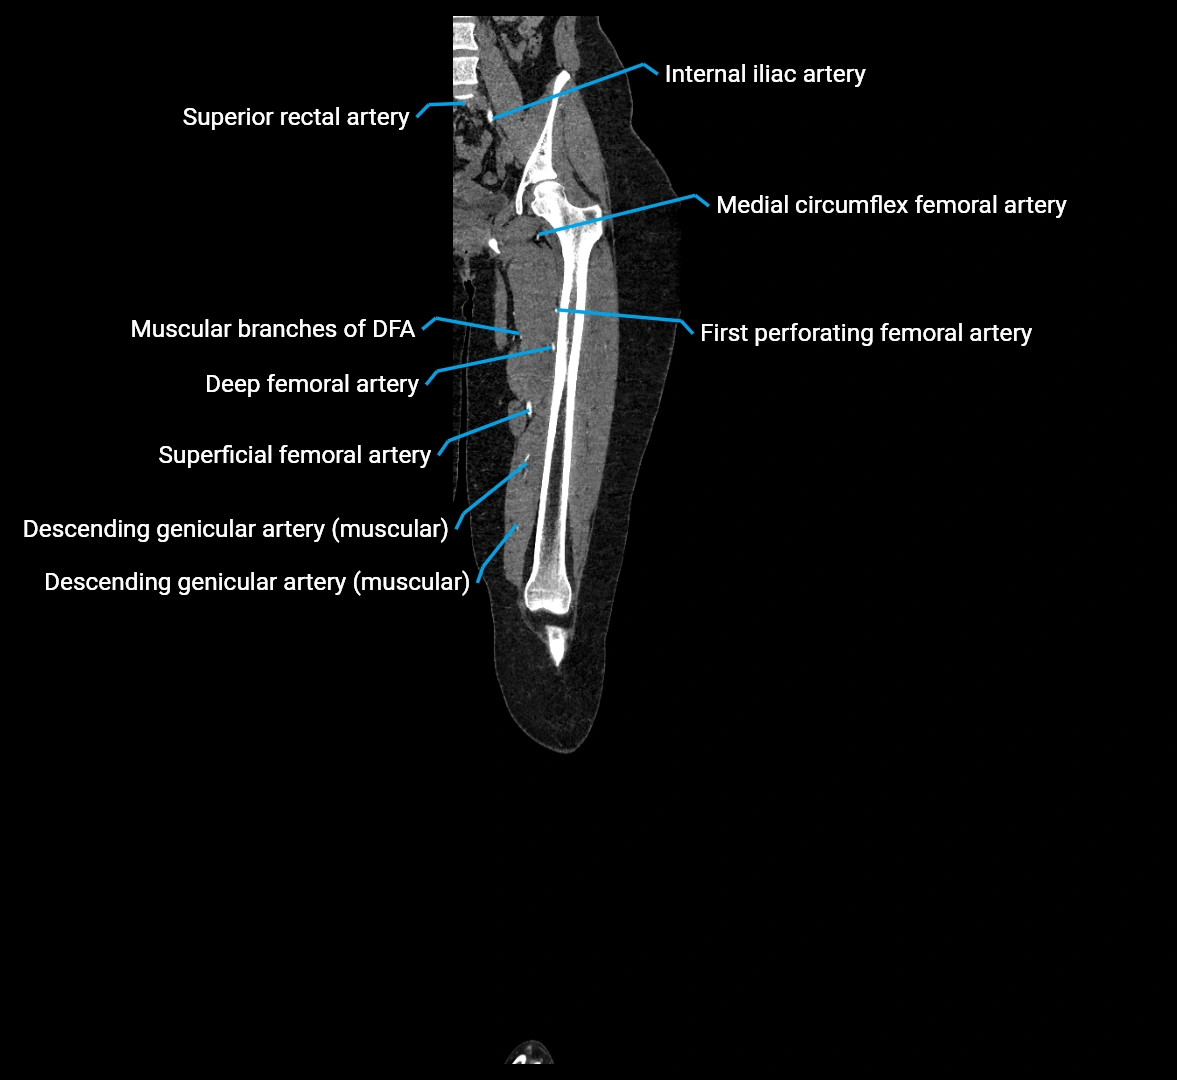

Contrast-enhanced CT (CTA):

• Gold standard for abdominal aortic imaging

• Provides excellent detail of lumen, wall, aneurysm, thrombus, and branch vessels

• Multiplanar and 3D reconstructions help in aneurysm measurement, stent graft planning, and dissection evaluation